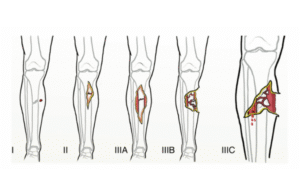

من أهم ملامح تحسين الممارسة الجراحية هو معرفة “متى لا نتدخل جراحياً”. دراسة POSTFIX الأخيرة حول كسور الكاحل الخلفية قدمت درساً هاماً: